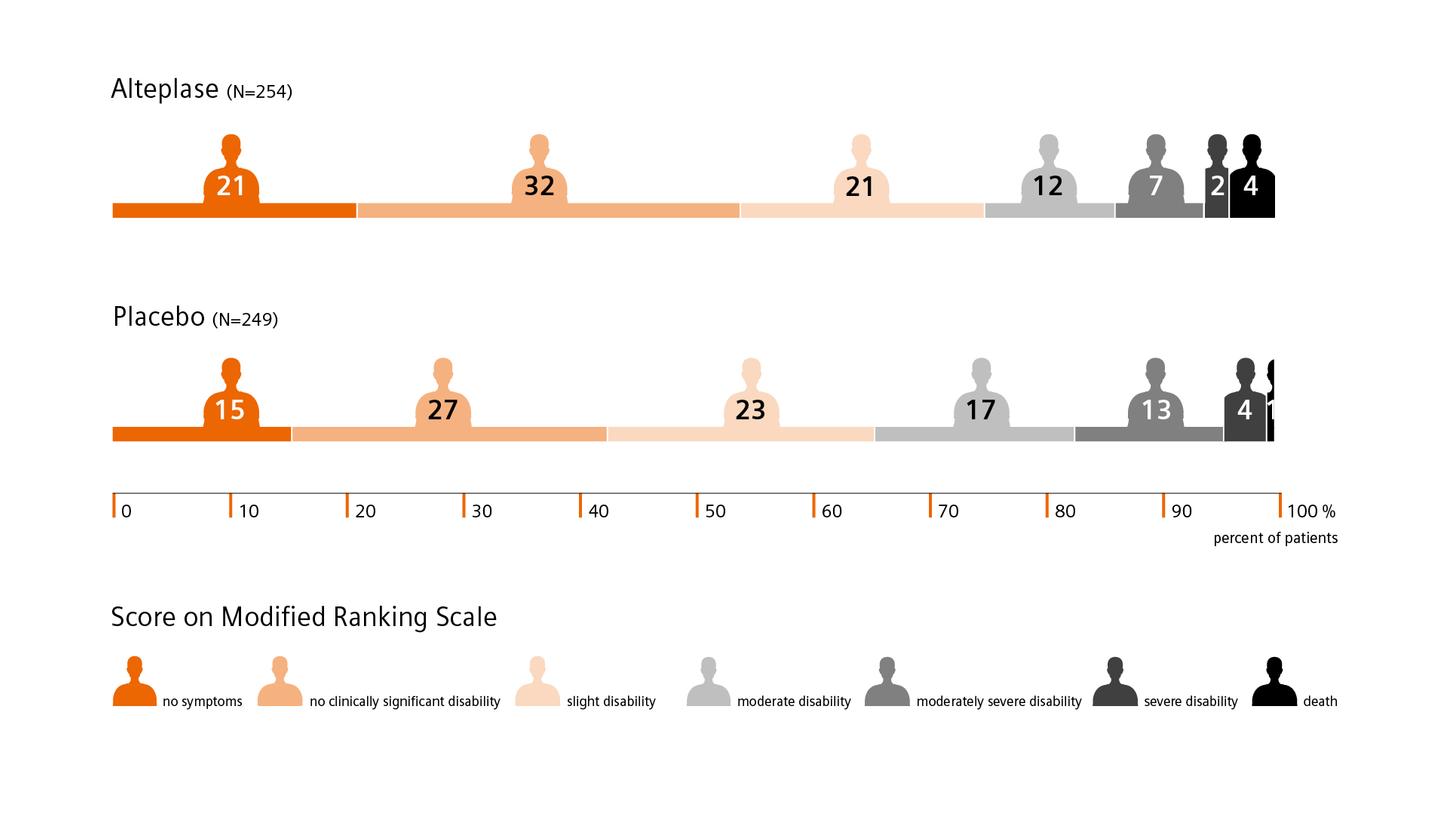

The WAKE-UP trial shows favorable outcomes for acute ischemic stroke patients with an unknown stroke onset: Patients identified by DWI-FLAIR mismatch on MRI with subsequent thrombolysis had significantly better functional outcomes than the placebo group.7

The WAKE-UP trial shows favorable outcomes for acute ischemic stroke patients with an unknown stroke onset: Patients identified by DWI-FLAIR mismatch on MRI with subsequent thrombolysis had significantly better functional outcomes than the placebo group.7

The WAKE-UP trial shows favorable outcomes for acute ischemic stroke patients with an unknown stroke onset: Patients identified by DWI-FLAIR mismatch on MRI with subsequent thrombolysis had significantly better functional outcomes than the placebo group.7